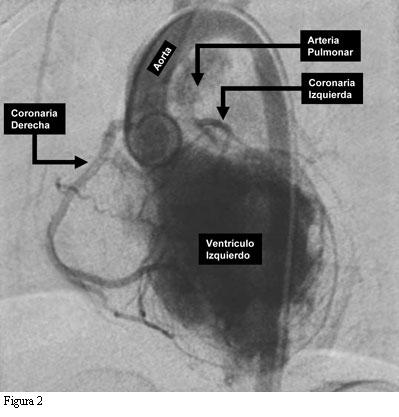

En base a la sospecha clínica basada en el ECG se indicó y realizó un cateterismo cardíaco. En la figura 2 se muestra una foto tardía de la ventriculografía izquierda luego de una inyección prolongada. Se observa el ventrículo izquierdo francamente dilatado, una aorta normal y la arteria coronaria derecha que se origina normalmente en la misma. Afuera y debajo del arco aórtico se observa un vaso que llega hasta la arteria pulmonar. Es la arteria coronaria izquierda que, con su flujo invertido, drena y tiñe débilmente la arteria pulmonar. En la figura 3 se muestra una coronariografía derecha selectiva en proyección oblicua izquierda. Allí se ve aun más claramente la arteria coronaria izquierda drenando en la arteria pulmonar.